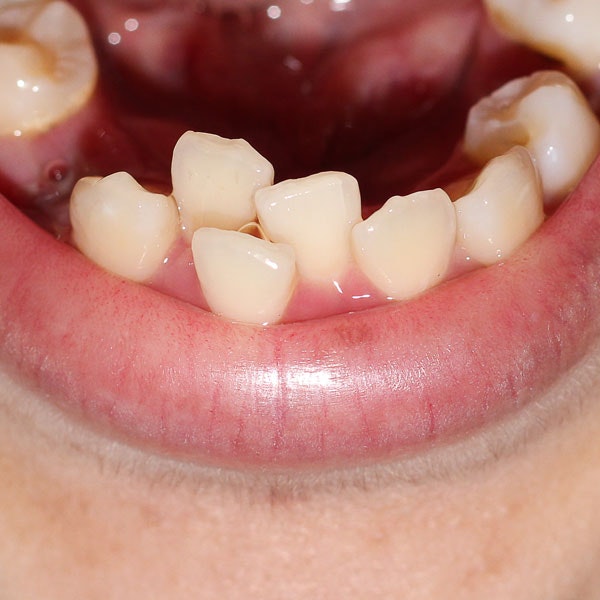

Receive a Simple Extraction

Non-impacted teeth are removed with a simple extraction that doesn't require an incision in the gums. After sedation and numbing, the dentist will gently rock the tooth back and forth out of the socket. Gauze is applied to help the blood clot and no stitches are required to stop the bleeding.